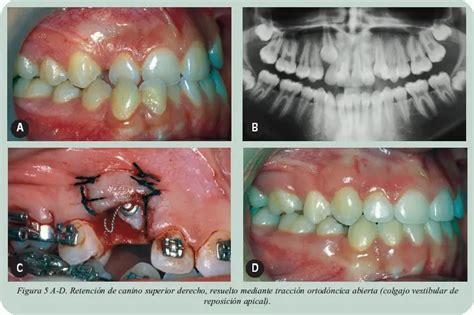

- Técnicas para exponer el canino maxilar incluido: Para caninos retenidos en el paladar, se pueden usar técnicas como gingivectomía, colgajo de reposición apical, técnica cerrada, técnica abierta y tunelización. La elección de la técnica depende de la posición y la cantidad de encía queratinizada.

Por el contrario, en la pregunta "Si tenemos un canino por vestíbulo en el tercio cervical del lateral, ¿qué técnica se decide?", la opción más seleccionada fue "técnica abierta" con una concordancia del 60 %. Según los mismos autores, esta técnica se decide cuando el canino se encuentra en una posición cefálica horizontal cercano al incisivo lateral. La mayor ventaja de esta técnica es la mejor visualización de la corona y una adecuada dirección del movimiento del canino8.

| Colgajo de Reposición Apical | Reposicionamiento del colgajo mucoperióstico | Caninos retenidos en el paladar |

| Técnica Abierta | Exposición completa de la corona del canino | Caninos en el tercio cervical del lateral por vestibular |